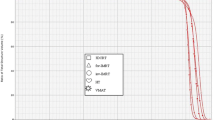

The dose distributions obtained with the different irradiation modalities are illustrated in Fig. 1 for a representative patient. The results indicate that a comparable and good coverage of the target volume is obtained independently of the radiotherapy technique or patient setup. The better conformity of PT is evident, as well as the significantly lower dose bath out-of-field compared to 3D-CRT and even more to VMAT. The OAR doses obtained with the different techniques are summarized in Table 1. As expected, the data indicate that OARs receive overall lower dose for Group 1, when SVC nodes only are included in the target. In this case, tangential 3D-CRT delivers a dose about 3 times higher than PT to the ipsilateral lung, while comparable doses below 1 Gy are obtained for the contralateral organs. Compared to Group 1, the PT dose to the ipsilateral lung increases by a factor 2.5–2.8 in Group 2 due to IMNs involvement, with a low dependence on patient setup (either FB or DIBH irradiation). Concerning photon irradiation, a dose about twice as high is observed for VMAT compared to PT. Remarkable differences between PT and VMAT are observed for contralateral OARs: while an average dose well below 1 Gy is delivered by PT, VMAT results in average doses of about 6–7 Gy and 5 Gy for the contralateral lung and breast, respectively, with a minor dependence on FB or DIBH. The dosimetric outcomes are further evidenced by the average cumulative DVHs reported in Fig. 2 for both treatment groups (the corresponding differential DVHs are reported in Additional file 1: Supplementary Figure S1).

Cumulative DVHs obtained averaging over the patients included in the study for Group 1 (left column) and Group 2 (right column). DVHs are shown for the ipsilateral lung (upper panel), contralateral lung (middle panel) and contralateral breast (lower panel). The different planning techniques are shown for each OAR. Please notice that different scales are adopted for the X-axis